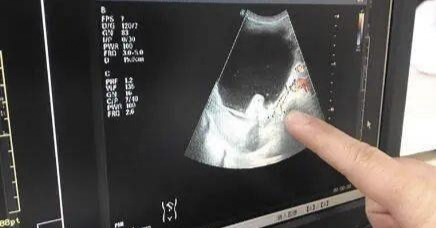

B超是超声的一种,又称为二维超声或灰阶超声,属于黑白成像。彩超是彩色多普勒超声的简称,但彩超可不是彩色的哦,它只是在B超的基础上加上彩色多普勒成像,即在B超显示的同时,还对血管产生红色和蓝色两种颜色,来表明不同的血流方向和流速,对疾病的诊断更加明确,应用也越来越广泛。

经阴道B超是棒状的探头经阴道接近子宫和卵巢,受肠道气体影响相对较小,且膀胱会影响探头接近子宫和卵巢,故需排空膀胱,因是通过阴道,在检查时候,医生会在表面套上一次性的乳胶套,防止病原体的传播。经阴道B超由于接近子宫和卵巢,图像清晰分辨率高,特别适合用于 检查子宫内膜等小病变以及检测卵泡发育的大小,但是若病变较大超出盆腔或因手术后粘连改变了子宫及卵巢的解剖位置时经阴道检查就无法完全探清了,无性生活者也不适用。